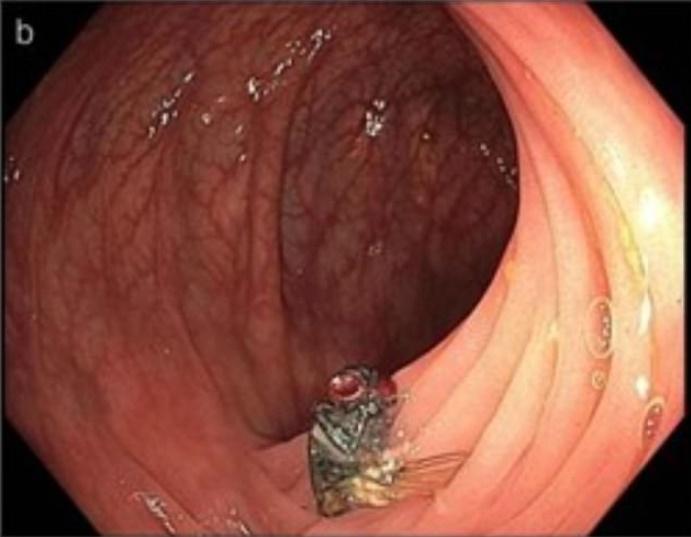

照大腸鏡其中一種常用和普及的身體檢查方法。美國密蘇里州卻出現一宗驚人病例,一名六旬漢接受例行性大腸鏡檢查時,竟然被發現腸道裡有一隻「活生生的烏蠅」,就連醫生都覺得難以置信,推測事主可能是之前吃到含有烏蠅幼蟲或卵的食物,才導致烏蠅在體內存活。

綜合報道,這名來自密蘇里州的63歲男子,今年初接受了大腸癌篩檢,醫生都會將攝影機放入腸內,檢查內部是否有病變、潰瘍或是長瘜肉等情形。然而,當醫生把攝影機深入橫結腸時,竟發現裡頭有一隻完整的烏蠅,而最令人震驚的是,牠是活生生在事主的腸道裡,令醫生驚訝不已。醫生事後向事主問診時,對方堅稱自己24小時前只有喝水,嚴守禁食規定,而且並不察覺肚子有異樣。不過,事主表示在更早之前,則吃幾塊披薩和一些生菜,因此醫生判定可能是烏蠅的幼蟲或卵殘留在食物中,經患者吃下肚後,在他的腸道內孵化成蛹,並成功長成一隻成年烏蠅。

這宗罕見案例已在《美國胃腸病學雜誌》(The American Journal of Gastroenterology)發表,案例中的醫生表示:「烏蠅究竟是如何完整地進入橫結腸中?」他指出,這種蛆蟲寄生在人類腸子裡的情況,通常是極為少見,畢竟蛆蟲需在有胃酸的環境下存活,幾乎不太可能。不過,美國疾病控制和預防中心(CDC)則表示,這些受感染者的反應盡不相同,有的人並不會有任何症狀,有些人則會出現腹痛、嘔吐和腹瀉等情形。而疾病預防中心的人員也呼籲,通常在較溫暖的月份,比較有可能把蛆蟲吃下肚,因此呼籲民眾務必把食材清洗乾淨。